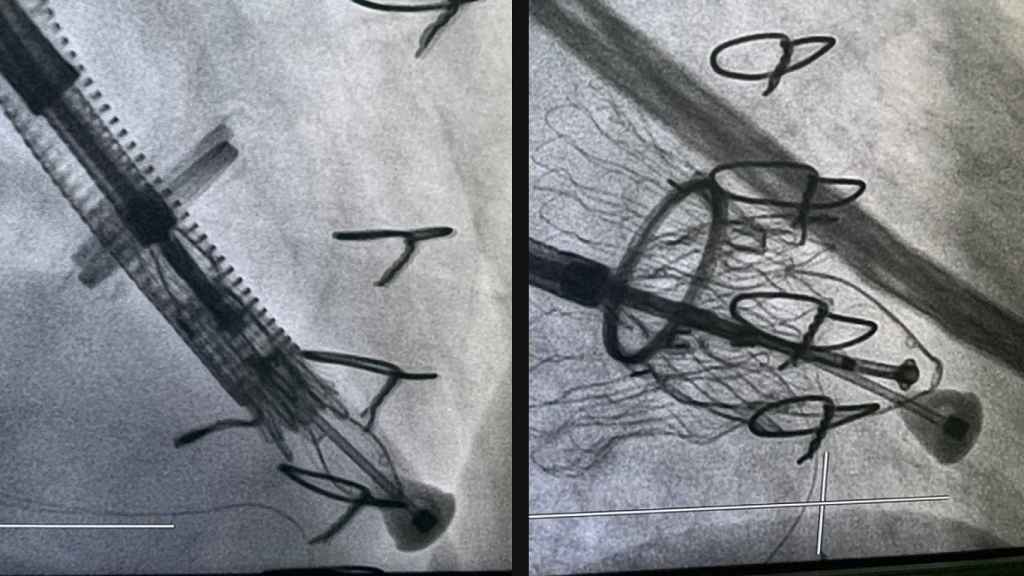

La novedad de la técnica empleada en el Hospital Vithas Vigo es la intervención percutánea, es decir, a través de un implante de una válvula biológica con técnicas de transcateter. A través de la vena yugular derecha, en el cuello, se introducen unos catéteres a través de los que se desplaza la válvula plegada hasta que está en la posición correcta. Una vez en la posición adecuada, se libera la válvula, que se expande por un mecanismo de autoexpansión y se ancla a la pared derecha del tabique intraventricular. De esta forma, la válvula comienza a funcionar correctamente y evita el reflujo se sangre del ventrículo a la aurícula, y mejora la circulación de la sangre hacia la arteria pulmonar.

Esta primera intervención se realizó a una mujer de 52 años que ya hace vida normal después de haber permanecido ingresada tan sólo una semana, totalmente asintomática y sin complicaciones postquirúrgicas. El Dr. Andrés Íñiguez, actual presidente de la Fundación Española del Corazón (FEC) y presidente de honor de la Sociedad Española de Cardiología (SEC), destaca que la técnica percutánea para la reparación de la válvula tricúspide tiene beneficios tanto para el paciente como para el médico, que no tiene que asumir los riesgos de una intervención abierta.